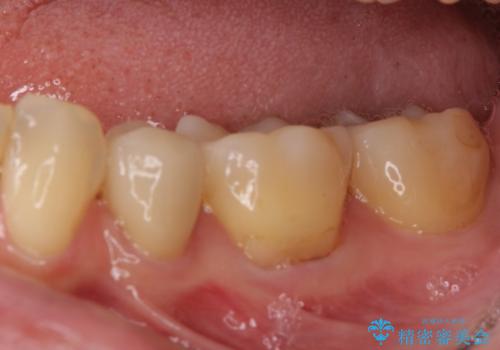

矯正治療後には、下顎臼歯の目立つ銀歯をセラミックインレーにて修復治療を行いました。

口を開けたときに金属が見えなくなり、患者様には大変満足していただきました。